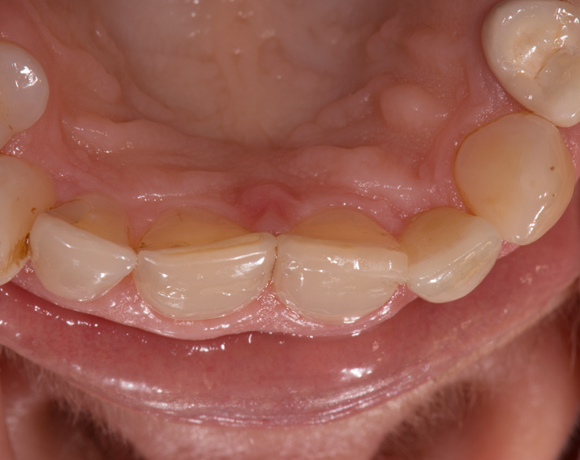

Zeramex T Implantat für Zahn 22

Einzelimplantate in der Front stellen oft ein Problem dar. Zirkonimplantate im Gegensatz zu Titanimplantate machen ästhetisch weniger Probleme, durch die weisse Farbe passen sie sich besser an das Zahnfleisch an.

Ein Projekt aus dem Jahr 2013

Im vorliegenden Patientenfall musste der Zahn 22 nach erfolgloser Endodontie entfernt werden. Die Nachbarzähne waren kariesfrei, es wurde eine Marylandbrücke (eine Brücke mit zwei Flügelchen, die palatinal an den Nachbarzähnen verklebt werden) oder ein Implantat besprochen. Die Patientin hat sich für ein Vollkeramikimplantat entschieden. In der Diashow wird der operative Eingriff bis zur fertigen Krone gezeigt. Die Einheilzeit betrug drei Monate.